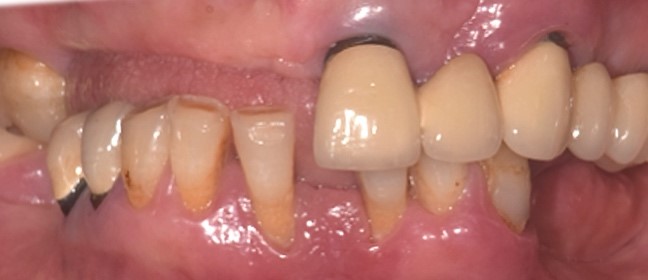

Una paziente di 65 anni si presentava presso la nostra clinica con ampie aree edentule (1° e 3° quadrante), un ponte con mobilità nel 2° quadrante e denti inferiori con scarso supporto parodontale ad eccezione del dente 46 (Fig. 1 a,b,c,d). Dopo un'accurata anamnesi ed esame della CBCT (CS9600®, Carestream Dental, Atlanta, USA) (Fig. 1d), si optava per estrarre le radici e i denti con una prognosi sfavorevole, lasciando 4 molari che credevamo potessero essere conservati (denti 16,17, 26 e 47) al fine di mantenere la dimensione verticale di occlusione (DVO) originale. Si progettava il posizionamento di 12 impianti: 6 impianti nella mascella e 6 nell'arcata inferiore.

Situazione pre operatoria 1

Fig. 1(a)

Situazione pre operatoria 2

Fig. 1(b)